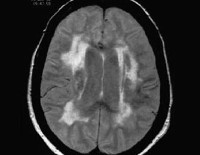

G21.4 Сосудистый паркинсонизм